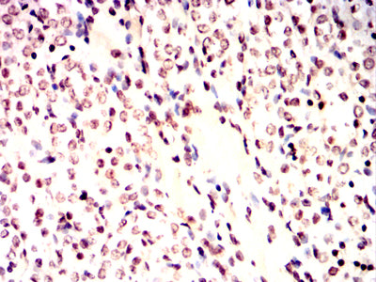

IHC    1/200 - 1/1000